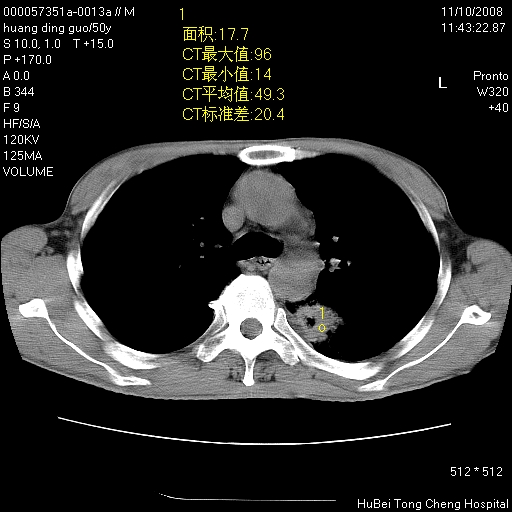

患者 男,50岁。左侧腰背部疼痛3月余,伴消瘦。平素健康,无传染病史。

胸部ct轴位平扫(层厚10mm,螺距1.5,重建间隔10mm),图像如下:

左肺下叶背段有一厚壁空洞,外壁呈锯齿状伴毛刺改变。空洞相邻胸膜有牵拉改变。左肺下叶血管支气管束不规则增粗,小叶间隔增厚。胸椎骨质破坏。考虑左肺下叶周围型肺癌伴左肺下叶癌性淋巴管炎、胸椎转移。

支持:左肺周围型肺癌伴癌性淋巴管炎\\胸椎转移瘤,不除外肺泡癌。(椎体破坏伴椎弓破坏)

左肺下叶背段有一厚壁空洞,外壁呈锯齿状伴毛刺改变。空洞相邻胸膜有牵拉改变。左肺下叶血管支气管束不规则增粗,小叶间隔增厚。胸椎骨质破坏。考虑左肺下叶周围型肺癌伴阻塞性肺炎、胸椎转移。其他待排

左肺下叶背段有一厚壁空洞,内壁不规则,外壁呈锯齿状伴毛刺改变。空洞相邻胸膜有牵拉改变。周围呈絮状炎性改变,左肺下叶血管支气管束不规则增粗,小叶间隔增厚。胸椎骨质破坏。考虑左肺下叶周围型肺癌伴左肺下叶阻塞性肺炎、胸椎转移。